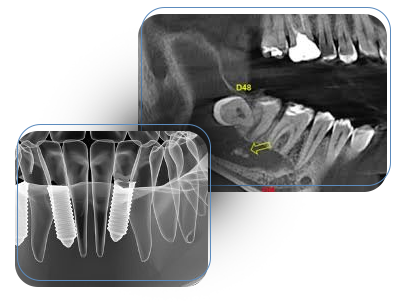

Consultoria em diagnóstico odontológico realizado por profissional experiente com apoio da IA para pacientes, acadêmicos e profissionais.

Dr. Natanael Átilas Aleva é cirurgião-dentista com mais de 30 anos de atuação acadêmica e clínica, doutor em Diagnóstico Bucal pela USP-SP, especialista em Estomatologia e Cirurgia Bucomaxilofacial. É também professor, mentor e idealizador do DiagnosIA, um projeto que une sua experiência acadêmica e prática com o que há de mais atual em inteligência artificial aplicada à Odontologia.